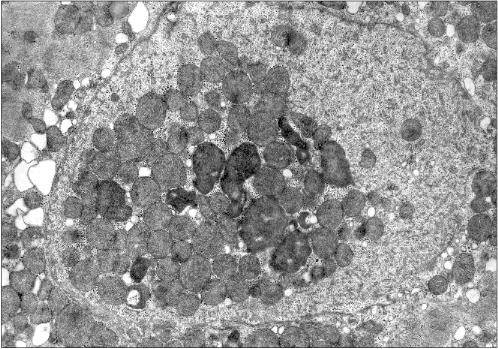

Figure 1 presents three patients' cardiomyocyte nuclei that contain mitochondrial clusters. Two patients were with hypertrophic cardiomyopathy and the third patient had alcoholic cardiomyopathy. One can see that the mitochondria are not separated by the nuclear membrane from the nuclear contents. This means that mitochondria are present in the nucleoplasm and not in a nuclear envelop invagination. All three microphotographs show the continuity of the nuclear membrane that separates the nuclear interior (with the mitochondria) from the cytosol.

Figure 1a

Fig. 1a. Intranuclear location of mitochondria in cardiomyocytes of patients with heart failure: patient G. (hypertrophic cardiomyopathy); ×48,000.

Examination of microphotographs of the mitochondria-containing nuclei shows that in most cases we are dealing with the cells that are entering apoptosis. Thus, most of the figures in the present article show chromatin margination (the accumulation at the edges of the nucleus) that is typical for apoptosis.